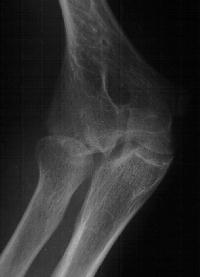

Initial injury: supracondylar fracture in a 9 year old:

Plain films show humeral osteophytes and posttraumatic changes of the capitellum and radial head.